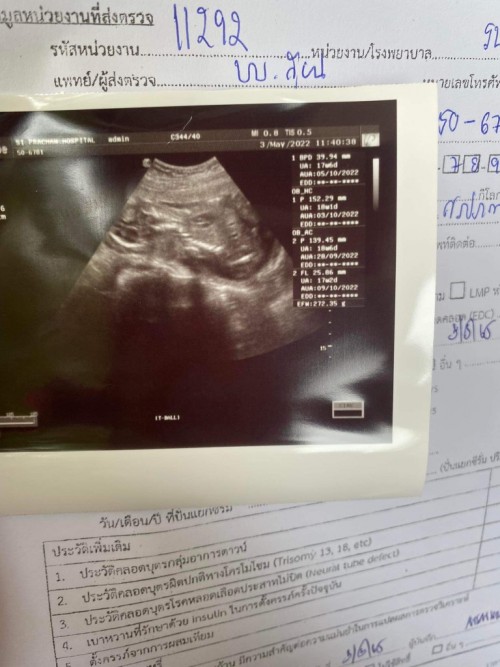

ภาพอัลตร้าซาวด์ปกติ

ขาวดำเหมือนกันค่ะ 22w